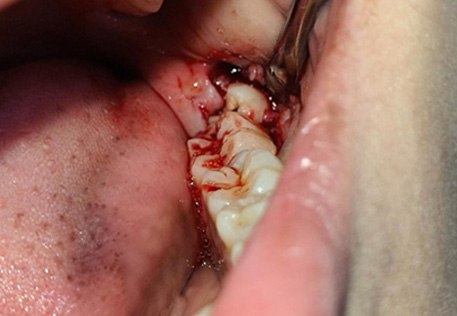

3. Wisdom Tooth Extraction (If Needed)

Simple Extraction: For fully erupted wisdom teeth that can be removed easily.

Surgical Extraction: For impacted or partially erupted wisdom teeth, performed with precision by our skilled oral surgeons.

Painless Procedure: Local anesthesia or sedation options for a comfortable experience.

Fast Recovery: Minimal downtime with post-treatment care guidance for a smooth healing process.